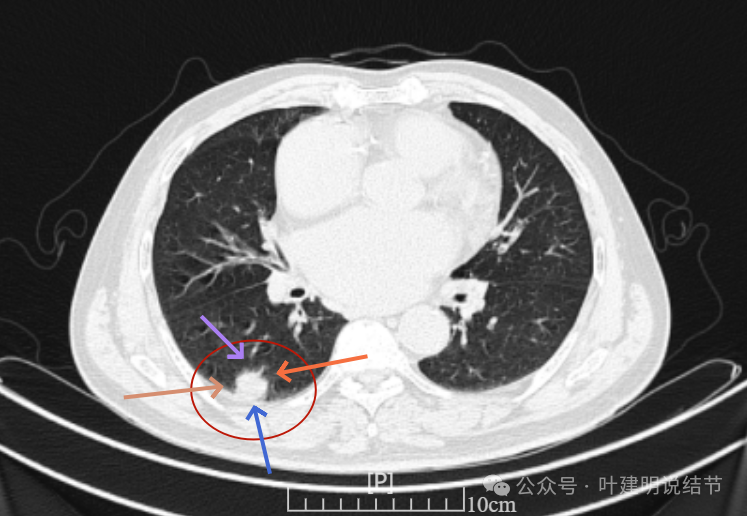

这是冠状位、矢状位与轴位的影像。

增强纵隔窗见病灶内部的密度好像低于周围区域,像坏死。

邻近胸膜无牵拉,灶内有低密度区,局部有点状液性密度。邻近胸膜较为广泛的增厚或胸膜反应。

病灶与胸膜接触面宽,病灶内部密度较低。